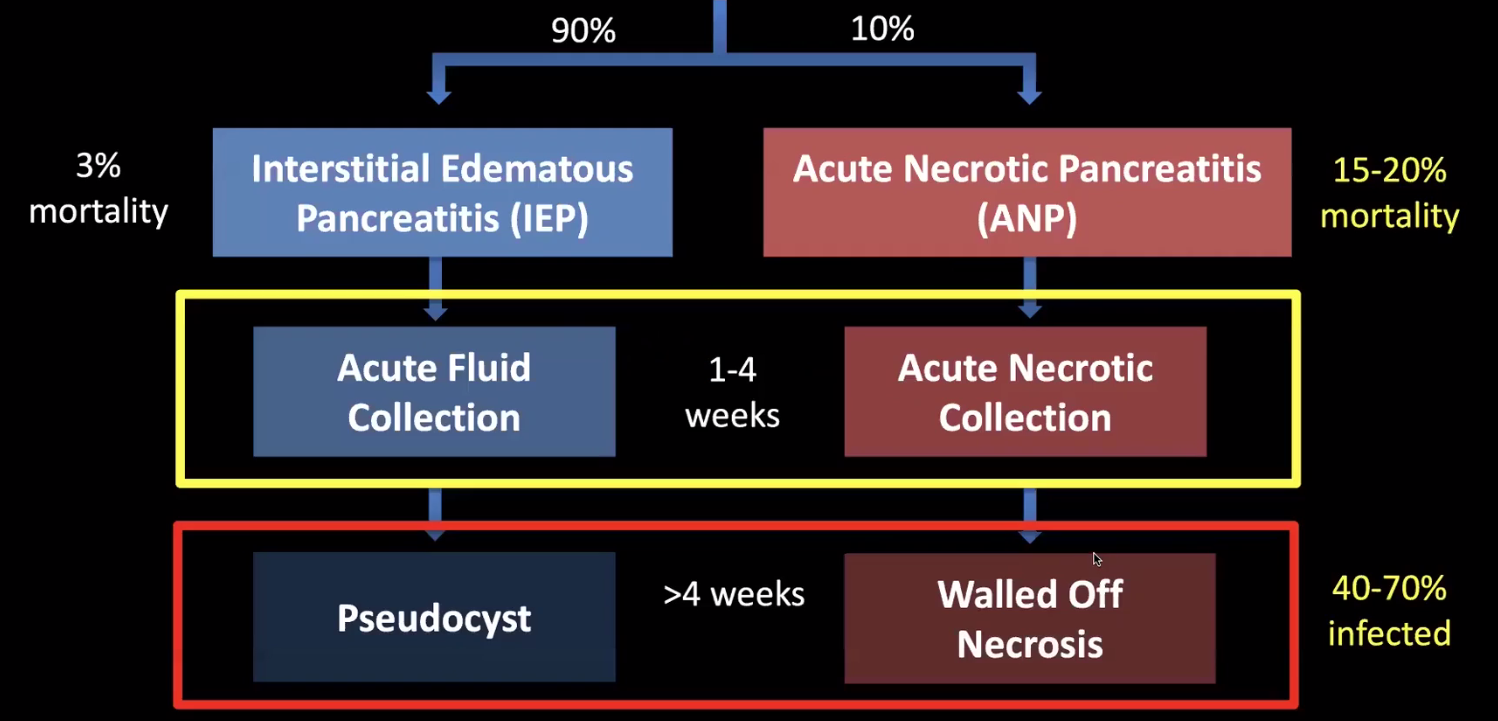

Collections

- Le CT est mauvais pour distinguer les collections liquidiennes de celles avec des débris

- Delai pour le staging: 48h

- Delai pour parler de pseudokystes: 4semaines

- Dans la pancreatite oedemato-interstitielle le liquide est limité autour du pancréas, et la complication en pseudokyte (vrai) est rare, et s’infectent très rarement

- Dans la pancreatite nécrosante, le liquide coule à distance du pancréas et fait la majorité des collections chroniques, qu’on apellait anciennement les pseudokystes mais qui sont des collections necrotiques cloisonées, qui peuvnet être steriles ou infectées

- Ne PAS drainer les pseudokystes simples sauf si symptomatiques